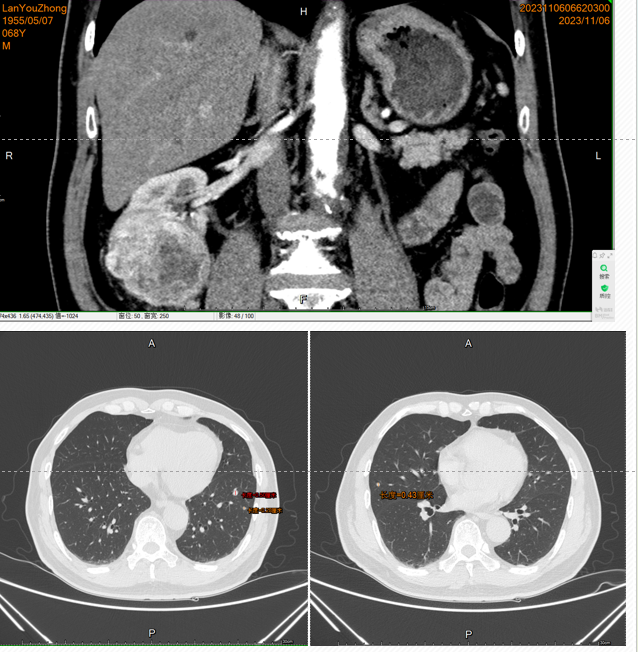

2023.11.06我院门诊就诊,肾CT增强:右肾下极见类圆形混杂密度影,大小约7.7x6.1cm,向肾外隆起,内见斑片状低密度灶,增强呈不均匀明显强化,延迟期强化减低。

右肾占位,考虑透明细胞癌可能。腹主动脉瘤可能。

2023.11.02肺CT:双肺多发散在小结节影,直径3-6mm,转移待排

• 2023-11-23腹腔镜下单侧肾切除术,术后病理:(右肾肿物)根治切除标本:透明细胞肾细胞癌,WHO/ISUP核分级4级,伴出血,未见明确脉管内癌栓及神经侵犯。癌侵犯未侵出肾纤维膜,未累及肾周脂肪囊,未累及肾盂黏膜及肾窦脂肪。输尿管切缘及血管切缘均未见癌;送检“右肾门淋巴结”未见转移癌(0/7)。免疫组化:CK-P(-),EMA(+),Vimentin(+),P63(-),RCC(+),PAX-8(+),CD117(个别细胞+),CK7(灶+),Ksp-Cad(+),CK20(-),SDHB(+),E-Cad(-),HMB45(-),P504s(-),Ki-67(+,约3%)。

• 2024.01复查肺CT:双肺肺内可见多处小结节影,大者直径约为11mm,考虑转移瘤可能。余脑/骨/全腹盆腔未见明确复发转移

• 确诊右肾透明细胞癌并双肺多发转移(T2aN0M1 IV期)。IMDC及MSKCC预后评分:2分(初始至开始系统性治疗时间<1年/贫血)、中危。